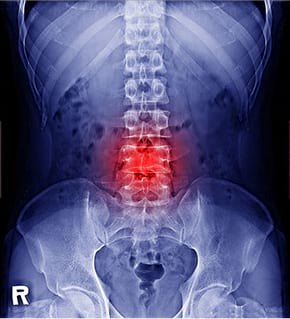

而手腕、脊椎和髖關節都是骨質疏鬆患者較易發生骨折的部位。值得留意的是,駝背和下背痛是長者常見的症狀,但這些症狀極可能是由脊椎壓縮性骨折(俗稱「冧骨」)所引致,進而導致脊椎變形。如不幸髖關節骨折,影響更大,會嚴重限制患者的行動能力。80歲以下的髖關節骨折患者中,約三成在一年後無法獨立行走,需要由家人照顧,另有二至四成需送入護老院。而髖骨骨折患者在術後1年的死亡率為17.3%,比香港同齡人口的死亡率(1.6%)約高出10倍1